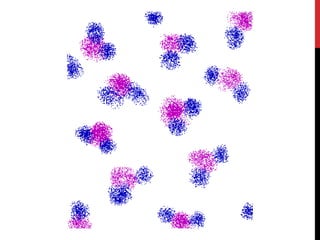

PROTONS ALIGNING WITHIN A MAGNETIC FIELD

In “field free” space

randomly oriented

• when placed in a magnetic field (B0; e.g., our MRI machines) protons will either align

with the magnetic field or orthogonal to it (process of reaching magnetic equilibrium)

• there is a small difference (10:1 million) in the number of protons in the low and high

energy states – with more in the low state leading to a net magnetization (M)

Inside magnetic field

oriented with or against B0

M = net magnetization

M

Applied Magnetic

Field (B0)

A top that is spinning slightly off the vertical axis is precessing about the vertical axis.

A hydrogen atom precesses about a magnetic field.

All of the hydrogen protons will align with the magnetic field in one direction or the other. The

vast majority cancel each other out, but, as shown here, in any sample there is one or two

"extra" protons.